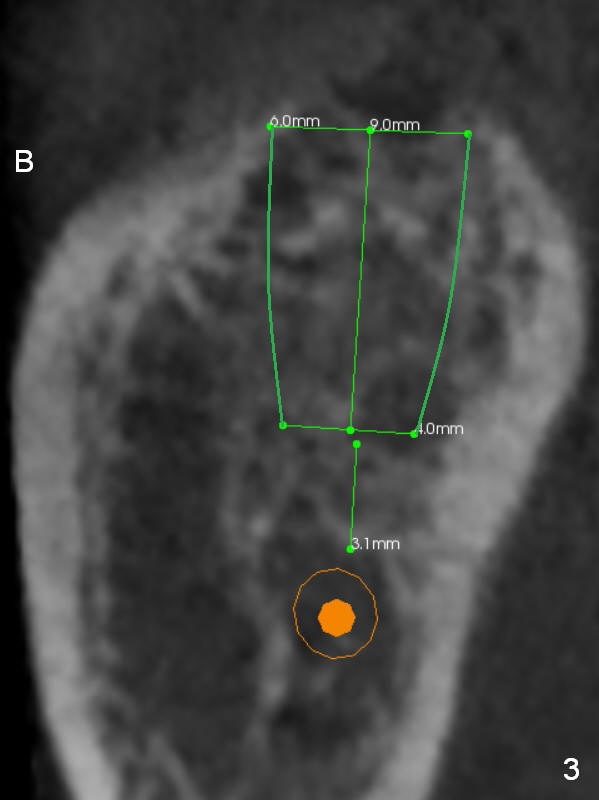

A 65-year-old woman is afraid of dentistry. After loss of the tooth #18 (Fig.1 with upper RPD), she feels necessary to have an implant (Fig.2). Since the ridge is wide (Fig.3), a flapless approach is adopted (Magic Split, measure the diameter of its handle). After 1.6 mm pilot drill (9 mm stopper) and Marking Drill (know the diameter of the large portion), use 4.8 mm Magic Drill (spacer set 2.5 mm, stopper 11 mm). Try in 5.5x9 mm dummy implant and most likely 6x9 mm definitive one.